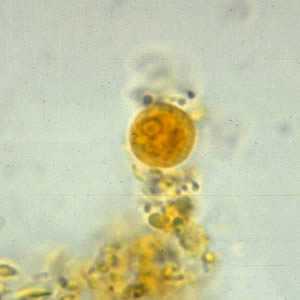

Iodamoeba buetschlii cysts in concentrated wet mounts.

Figure A: Cyst of I. buetschlii in an unstained concentrated wet mount. In these cysts, the glycogen vacuole can be seen as a large, oval refractile body.

Figure B: Cyst of I. buetschlii in an unstained concentrated wet mount. In these cysts, the glycogen vacuole can be seen as a large, oval refractile body.

Figure C: Cyst of I. buetschlii from the same specimen as seen in Figures A and B, but stained with iodine. In this cyst, the glycogen vacuole is more-easily observed as a dark-staining mass in the cyst.

Figure D: Cyst of I. buetschlii from the same specimen as seen in Figures A and B, but stained with iodine. In this cyst, the glycogen vacuole is more-easily observed as a dark-staining mass in the cyst.